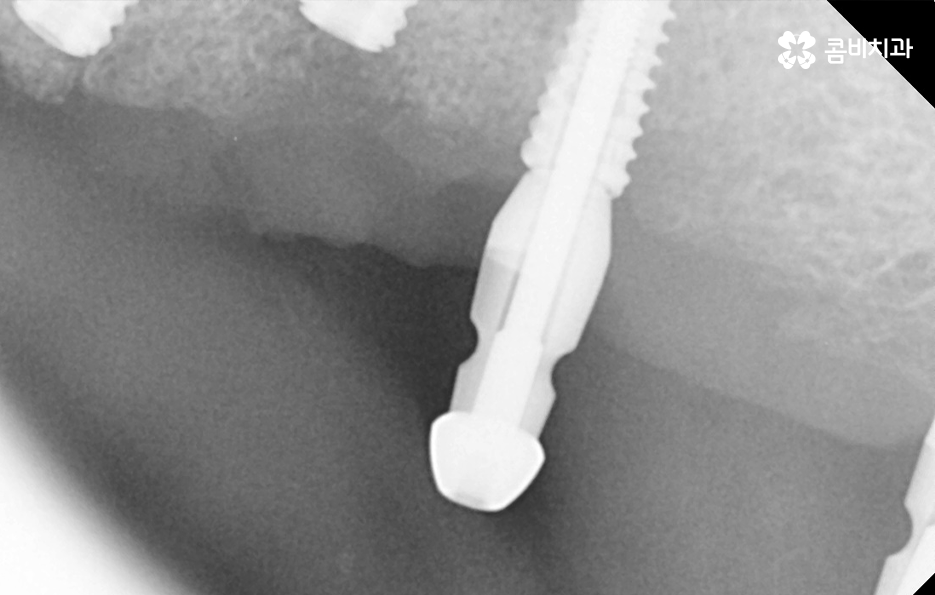

실제 치료 사례를 살펴보더라도 젊은 환자분들의 경우 원데이임플란트로도 치료가 가능한 사례가 많다면 노인분들의 경우 잇몸이 약해진 상태에서 치주염으로 치아를 잃게 된 경우가 많다보니 뼈이식을 추가적으로 받아야 하는 경우가 많이 있어요

임플란트의 치료 과정에서 중요한 부분은 잇몸 뼈에 임플란트 인공치근을 식립하여 골유착 과정을 안전하게 거쳐야 하기 때문에 잇몸 뼈의 중요성이 그만큼 크다고 할 수 있는데요

5,60대 이후 환자 분들의 경우에는 잇몸 상태가 이미 좋지 않은 분들이 많고 전신질환이 있는 분들도 많기 때문에 임플란트 나이에 있어서는 보다 섬세한 치료가 필요한 경우가 좀더 많다고 볼 수 있어요